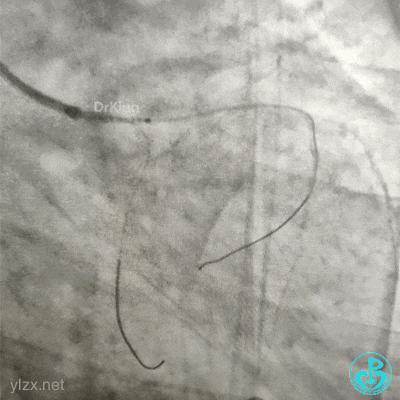

交换导丝后扩支架网眼。

结束手术。

下台时血压127/78mmHg,心率75次/分。